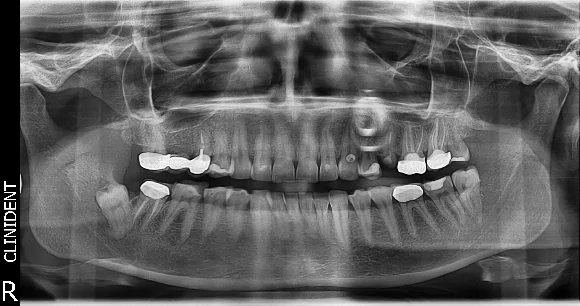

A fiatal és igen aktív életet élő hölgy páciensem azért jelentkezett hozzánk az első konzultációjára, mert a bal felső, második kisörlő (25-ös) foga letörött.

A letört fog korábban, máshol már gyökérkezelésen is átesett.

A letört fog alaposabb vizsgálata után a fog eltávolítása mellett döntöttünk. A foghúzás utáni gyógyulási időre egy speciális ideiglenes fogpótlás, az ún. klipsz viselését javasoltam.

A műgyökér gyógyulási idejére, a vele ellentétes oldalon található rossz fém-kerámia híd cseréjét és néhány fogtömést is beterveztünk.